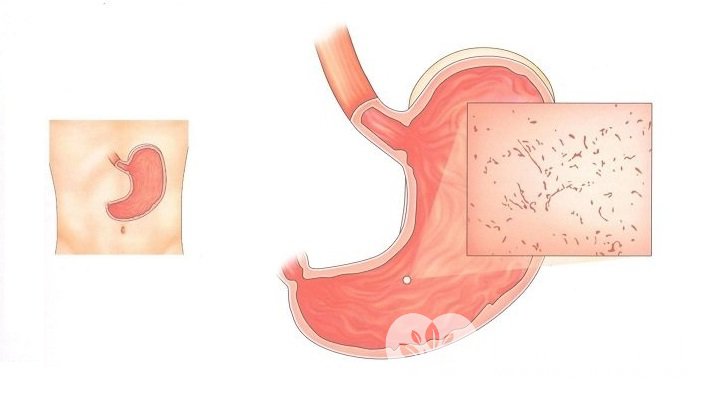

Информация и фотографии о хроническом гастрите и дуодените